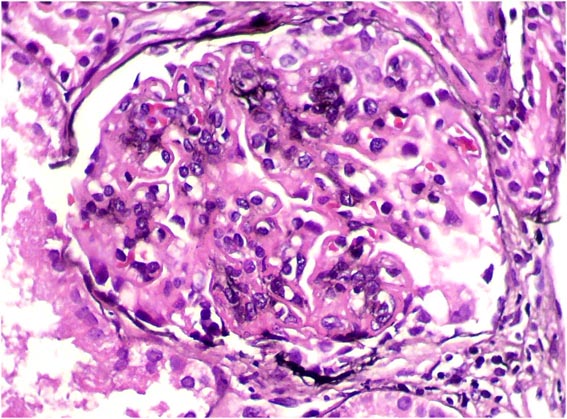

Observe las imágenes de esta

segunda biopsia.

Figura 1.

H&E, X100.